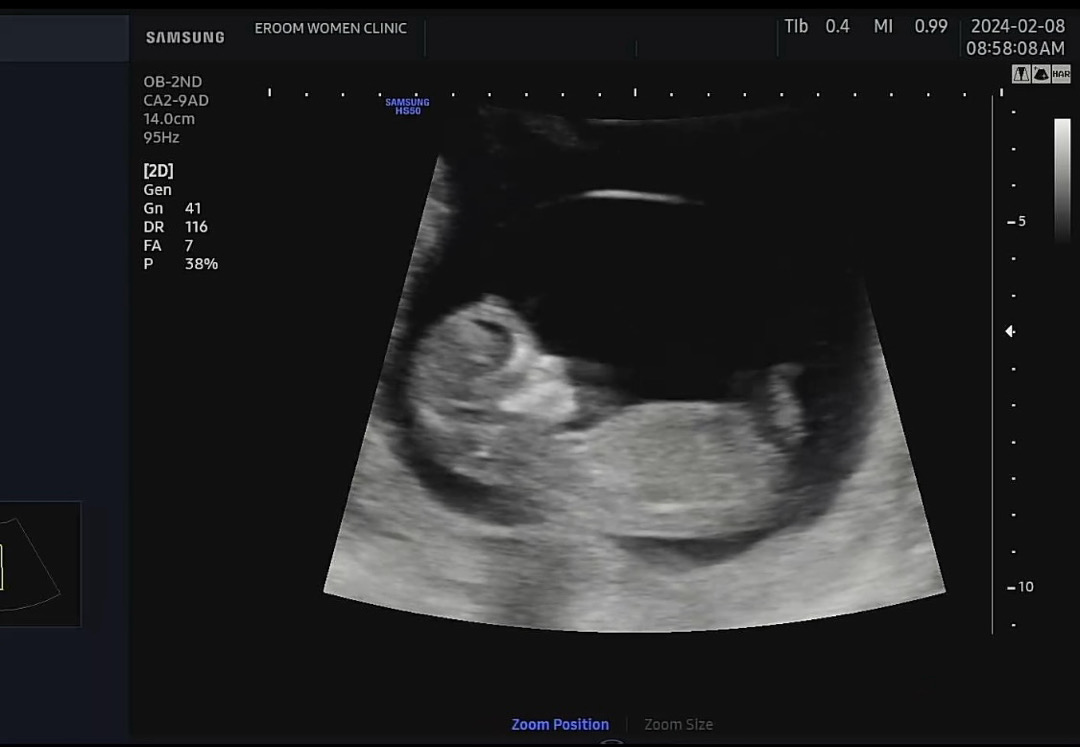

12주차 4일 각도법 의견 부탁드려요

엄마 하이👋🏻하듯 영상에서는 손을 흔들고 잌ㅅ었어요~ 12주차 4일 얼굴 옆모습 넘 귀여워서 벌써 도치맘될거 같아요. 이 사진으로는 각도법 알 수 있을까요? 조언 부탁드립니다🙏🏻 명절 잘 보내세요!!